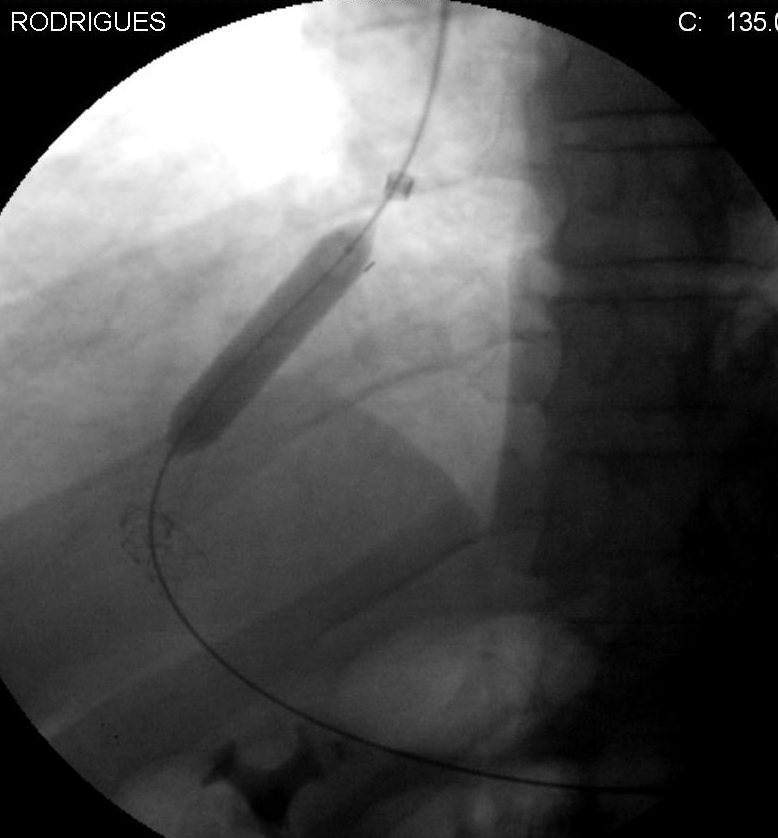

TIPS vs DSRS 在门脉高压再出血预防随机对照显示(食道静脉曲张再出血N=140,Child Pugh A/B)对预防再出血两者都有效,DSRS再出血率5.5%,TIPS再出血率10.5%。肝性脑病和生存率两者无差异【1】。 预防再出血 外科分流 和TIPS vs 内窥镜治疗【2】 ![]() 治疗顽固性腹水 TIPS vs 腹腔引流术【3】 ![]() TIPS 术前检查 心脏、肝、肾功能评价; 有无肝性脑病、EDA、麻醉前检查 TIPS术前影像 肝静脉和门静脉是否通畅 (1)多普勒超声:门静脉血流方向、门静脉血流速度、肝静脉和门静脉解剖关系。 (2)经动脉间接门静脉造影 (3)二氧化碳 门静脉造影 (4)CTA 门静脉重建 ![]() TIPS 技术上考虑 1. TIPS穿刺前 (1) 清醒镇定/ 全麻 (2) 术前和术后肝静脉压力梯度测定 (3)生命体征监测 (4)门静脉造影 (5)超声或透视引导下门静脉穿刺(标记门静脉) 2. TIPS穿刺 (1)右颈静脉穿刺 (2)右肝静脉造影 (3)经右门静脉穿刺门静脉

注意门静脉分叉分类 ![]() (4).穿刺成功后引入导丝 (5) 经导丝引入导管

(6) 测量门静脉压力

(7)球囊导管扩张

(8) 支撑架释放 ![]() 支撑架直径8-10mm